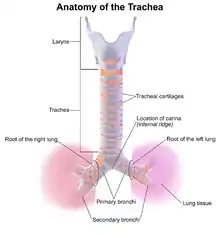

Anatomy

The trachea and bronchi form the tracheobronchial tree. The trachea is situated between the lower end of the larynx and the center of the chest, where it splits into the two bronchi at a ridge called the carina. The trachea is stabilized and kept open by rings made of cartilage that surround the front and sides of the structure; these rings are not closed and do not surround the back, which is made of membrane.[21] The bronchi split into smaller branches and then to bronchioles that supply air to the alveoli, the tiny air-filled sacs in the lungs responsible for absorbing oxygen. An arbitrary division can be made between the intrathoracic and cervical trachea at the thoracic inlet, an opening at the top of the thoracic cavity.[17] Anatomical structures that surround and protect the tracheobronchial tree include the lungs, the esophagus, large blood vessels, the rib cage, the thoracic spine, and the sternum.[17] Children have softer tracheas and a more elastic tracheobronchial trees than adults; this elasticity, which helps protect the structures from injury when they are compressed, may contribute to the lower incidence of TBI in children.[21]